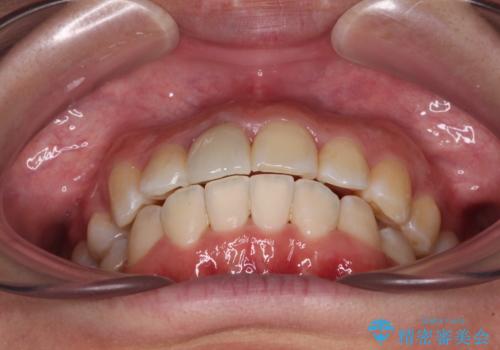

口元の突出感は少なく、下顎の叢生は軽微なものであったので、叢生の強い上顎左右の小臼歯を1本ずつ抜歯し、ワイヤー装置にて矯正治療を行うこととしました。

矯正治療を行う前に、根管治療の必要な上顎前歯と下顎大臼歯の根管治療を行い、矯正治療の途中で下顎の欠損部にインプラント埋入することとし、矯正治療後に補綴治療を行うこととしました。

矯正治療中にインプラント埋入を行うなど、余計な時間や無駄のない治療を行うことができました。